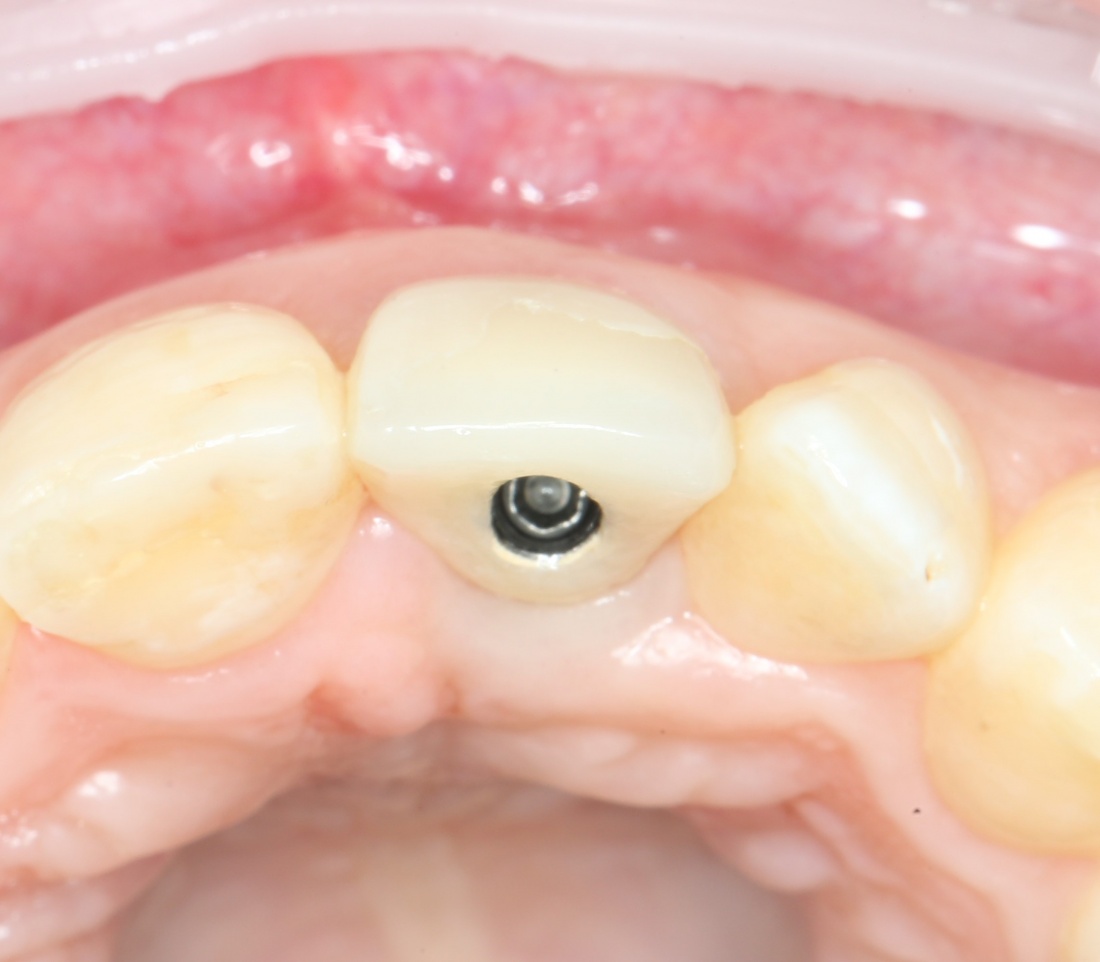

Рекомендации по установке имплантов. Для всех. Часть V.